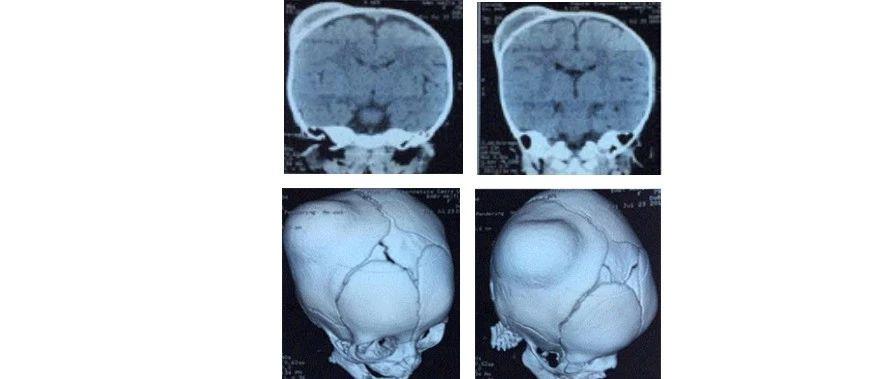

新生儿头颅血肿是一种常见的产伤 ,通常发生在分娩过程中。当胎儿头部在产道中受到挤压或使用产钳等助产工具时,可能会导致头颅骨膜下的血管破裂,血液积聚形成血肿。这种状况在新生儿中并不少见,国内数据显示其发生率在2.5%到2.8%之间。

头颅血肿的自然愈合过程大致如下:在出生后的几小时到几天内,血肿会逐渐增大,达到最大范围后开始缓慢吸收。这个过程可能需要几周到几个月的时间。在愈合过程中,血肿的边缘可能会出现钙化或骨化现象,形成硬块。但通常情况下,这些小的骨化并不会导致头颅畸形,也不会影响到颅骨发育。